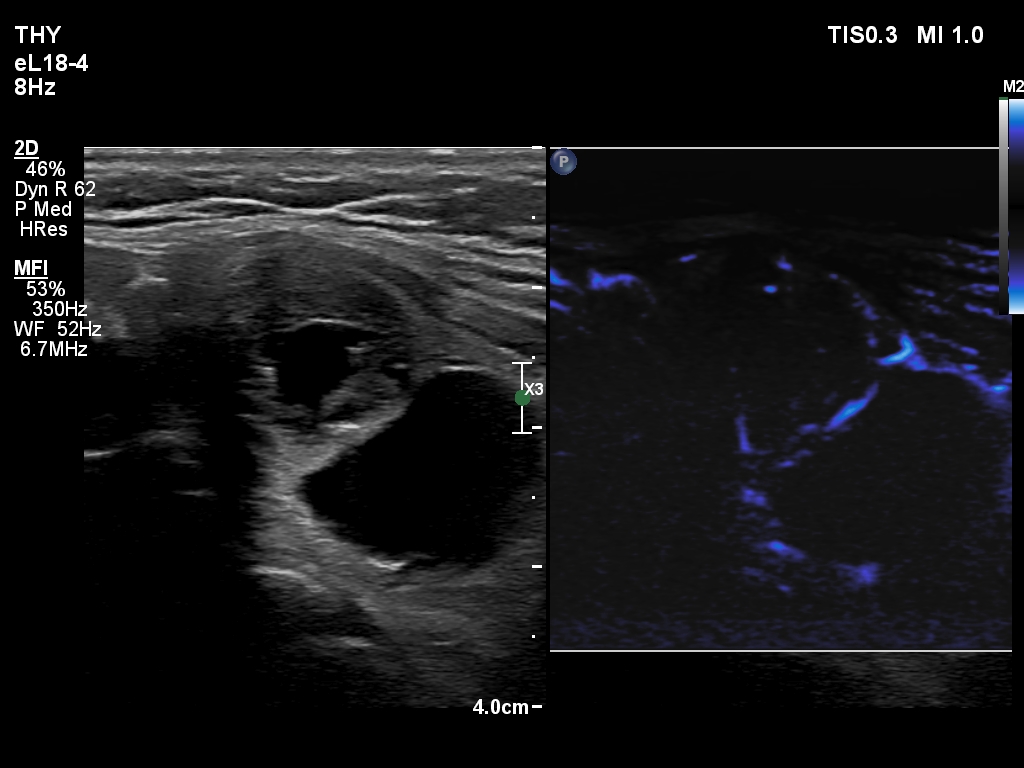

The composition of the nodule - case 2179 (ultrasonographic picture 18)

Right lobe, longitudinal scan

Middle-lower part of the left lobe, transverse scan, microflow imaging.